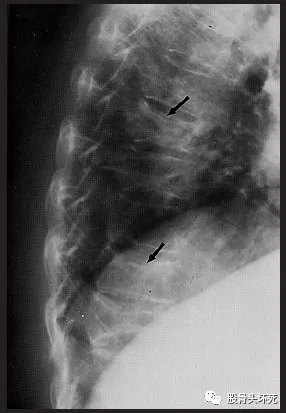

压缩骨折的放射学影响特征包括:一个或多个椎体前端楔形变伴椎体塌陷、椎体终板不规则和整体脱矿化。

椎体骨折的严重程度可按放射影像学表现分级:

●1级–脊柱高度降低20%-25%的畸形

●2级–脊柱高度降低25%-40%的畸形

●3级–脊柱高度降低>40%的畸形